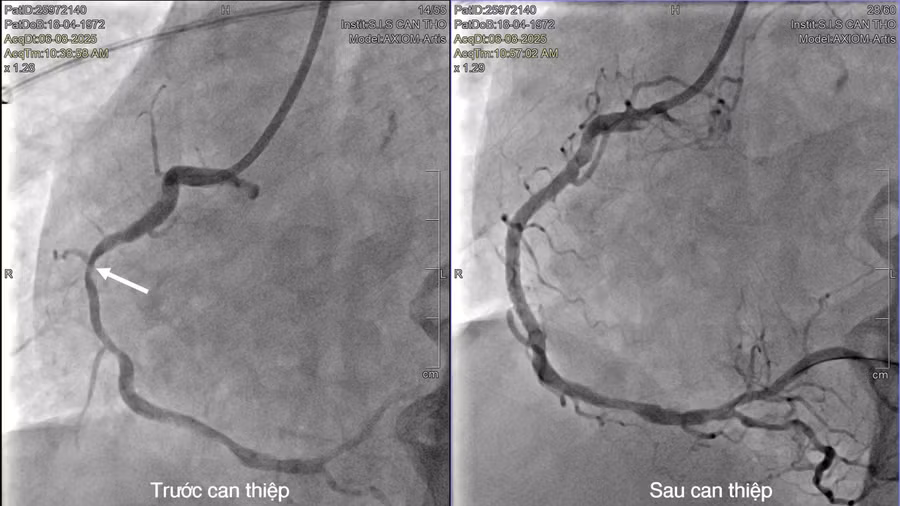

Tại S.I.S Cần Thơ, điện tim ghi nhận bệnh nhân bị nhồi máu cơ tim ST không chênh lên thành dưới, biến chứng rối loạn nhịp nguy hiểm. Chụp mạch vành qua hệ thống DSA cho thấy, cả 3 nhánh mạch vành hẹp nặng, phức tạp, nhưng mạch máu đã tự tái thông dòng chảy.

Qua khai thác bệnh sử, ghi nhận khoảng 2 ngày trước khi xảy ra ngưng tim, bệnh nhân có biểu hiện sốt và rét run. Nhằm xác định chính xác nguyên nhân ngưng tim, liệu do viêm cơ tim, sốc nhiễm trùng hay nhồi máu cơ tim, các bác sĩ đã chỉ định chụp MRI tim. Kết quả cho thấy, tổn thương cơ tim bắt nguồn từ tình trạng hẹp nặng động mạch vành bên phải.

Ê-kip can thiệp đã tiến hành đặt stent tái thông thành công một nhánh động mạch vành bị hẹp. Sau 2 tuần điều trị tích cực, bệnh nhân hồi phục tốt, tỉnh táo, không di chứng não. Các tổn thương mạch vành còn lại sẽ được can thiệp ở giai đoạn tiếp theo.